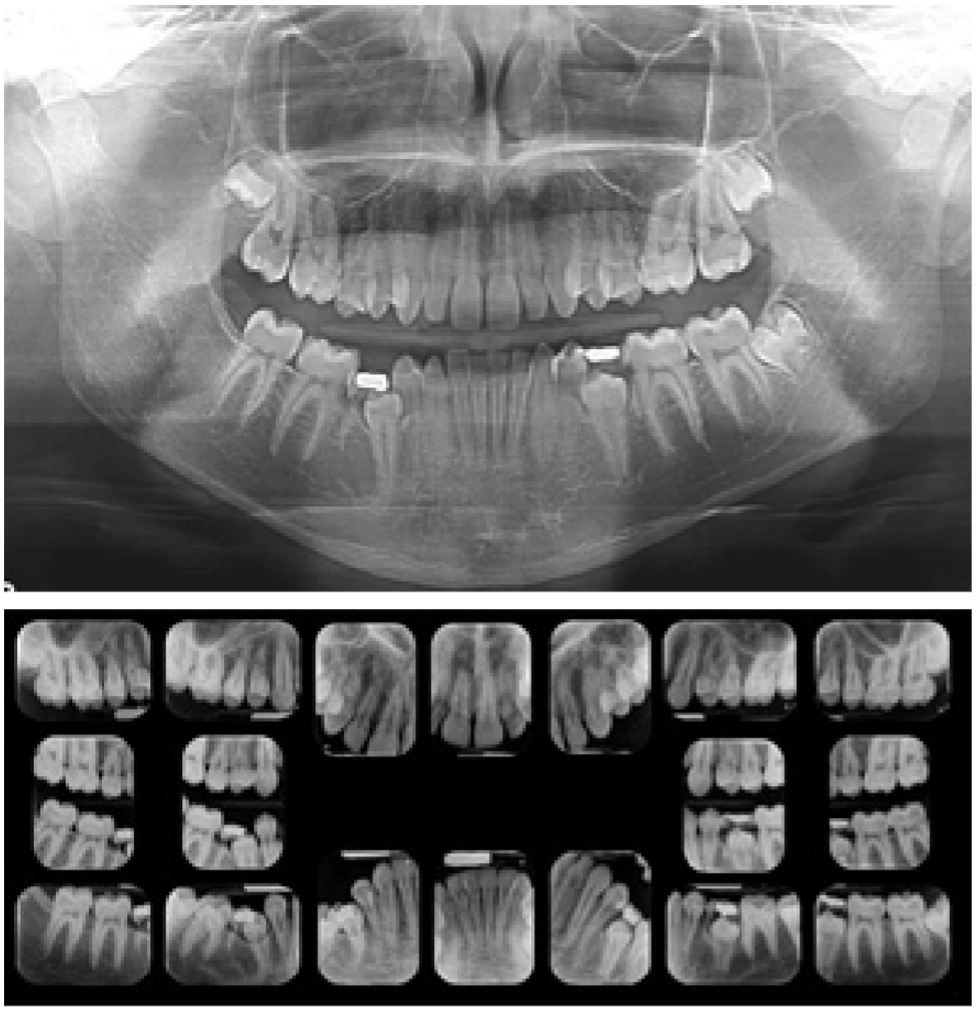

Caso 1. Paciente femenino de 13 años referida por el odontopediatra para consultar la posición de los caninos superiores. Los padres refieren perfecto estado de salud y que la paciente no tuvo tratamiento de ortodoncia u ortopedia previo, durante la anamnesis se reportó solamente alergia al maní. Entre sus antecedentes familiares, los padres fueron tratados ambos con ortodoncia y la madre refiere agenesia de terceros molares superiores. La hermana del paciente fue tratada por impactación unilateral de canino superior derecho con agenesia de incisivo lateral superior derecho. Los padres firmaron consentimiento informado. Al momento del diagnóstico, la paciente presentó una maloclusión Clase I, con impactación bilateral palatina de caninos superiores en el sector 3 del Índice de Ericson & Kurol,13 asociada a incisivos laterales superiores estrechos mesio- distalmente (microdónticos), infra-oclusión del segundo molar primario inferior izquierdo. Además un segundo premolar inferior izquierdo impactado, asociado a un patrón distal de erupción (Figura 1). El tratamiento consistió en: remoción del segundo molar primario inferior izquierdo, expansión palatina rápida, terapia ortodóncica con aparatología fija .022 de Straightwire, y la exposción quirúrgica para tracción de ambos caninos superiores impactados.

Figura 1. Panorámica inicial donde se observa segundo premolar inferior izquierdo impactado asociado a incisivos laterales superiores microdónticos e infra-oclusión del segundo molar primario inferior izquierdo.

Caso 2. Paciente femenino de 14 años referida por familiar endodoncista quien nota la alteración de la erupción al evaluarla. La madre firmó el consentimiento informado. Tuvo tratamiento previo con rejilla lingual para hábito de succión. En la anamnesis la paciente reporta problemas gastrointestinales y acude regularmente a sus controles pediátricos. Padre y madre tuvieron ortodoncia por apiñamiento leve. La hermana también tuvo tratamiento de ortodoncia, con incisivo lateral superior derecho microdóntico, el cual fue reconstruido con resina post-ortodoncia para aumentar su ancho mesio-distal. Al momento de la consulta la paciente presentó como diagnóstico: maloclusión Clase I con mordida abierta anterior asociada a la presencia del hábito de succión del dedo pulgar, con incisivos laterales superiores estrechos mesio-distalmente, con agenesia del segundo premolar inferior derecho y retención prolongada del segundo molar inferior derecho primario, el cual se encuentra en infraoclusión, presentando un segundo premolar inferior izquierdo impactado con patrón eruptivo distal del segundo molar inferior derecho. En la radiografía panorámica y periapical puede apreciarse el antes y después de tratamiento (Figura 2). El tratamiento consistió en: remoción del segundo molar primario inferior izquierdo, terapia ortodóncica con aparatología fija .022 de Straightwire y la exposición quirúrgica para tracción del segundo premolar inferior izquierdo.

Figura 2: Radiografía panorámica y periapical iniciales y finales, mostrando la resolución de la impactación del segundo premolar inferior izquierdo, con patrón eruptivo distal.